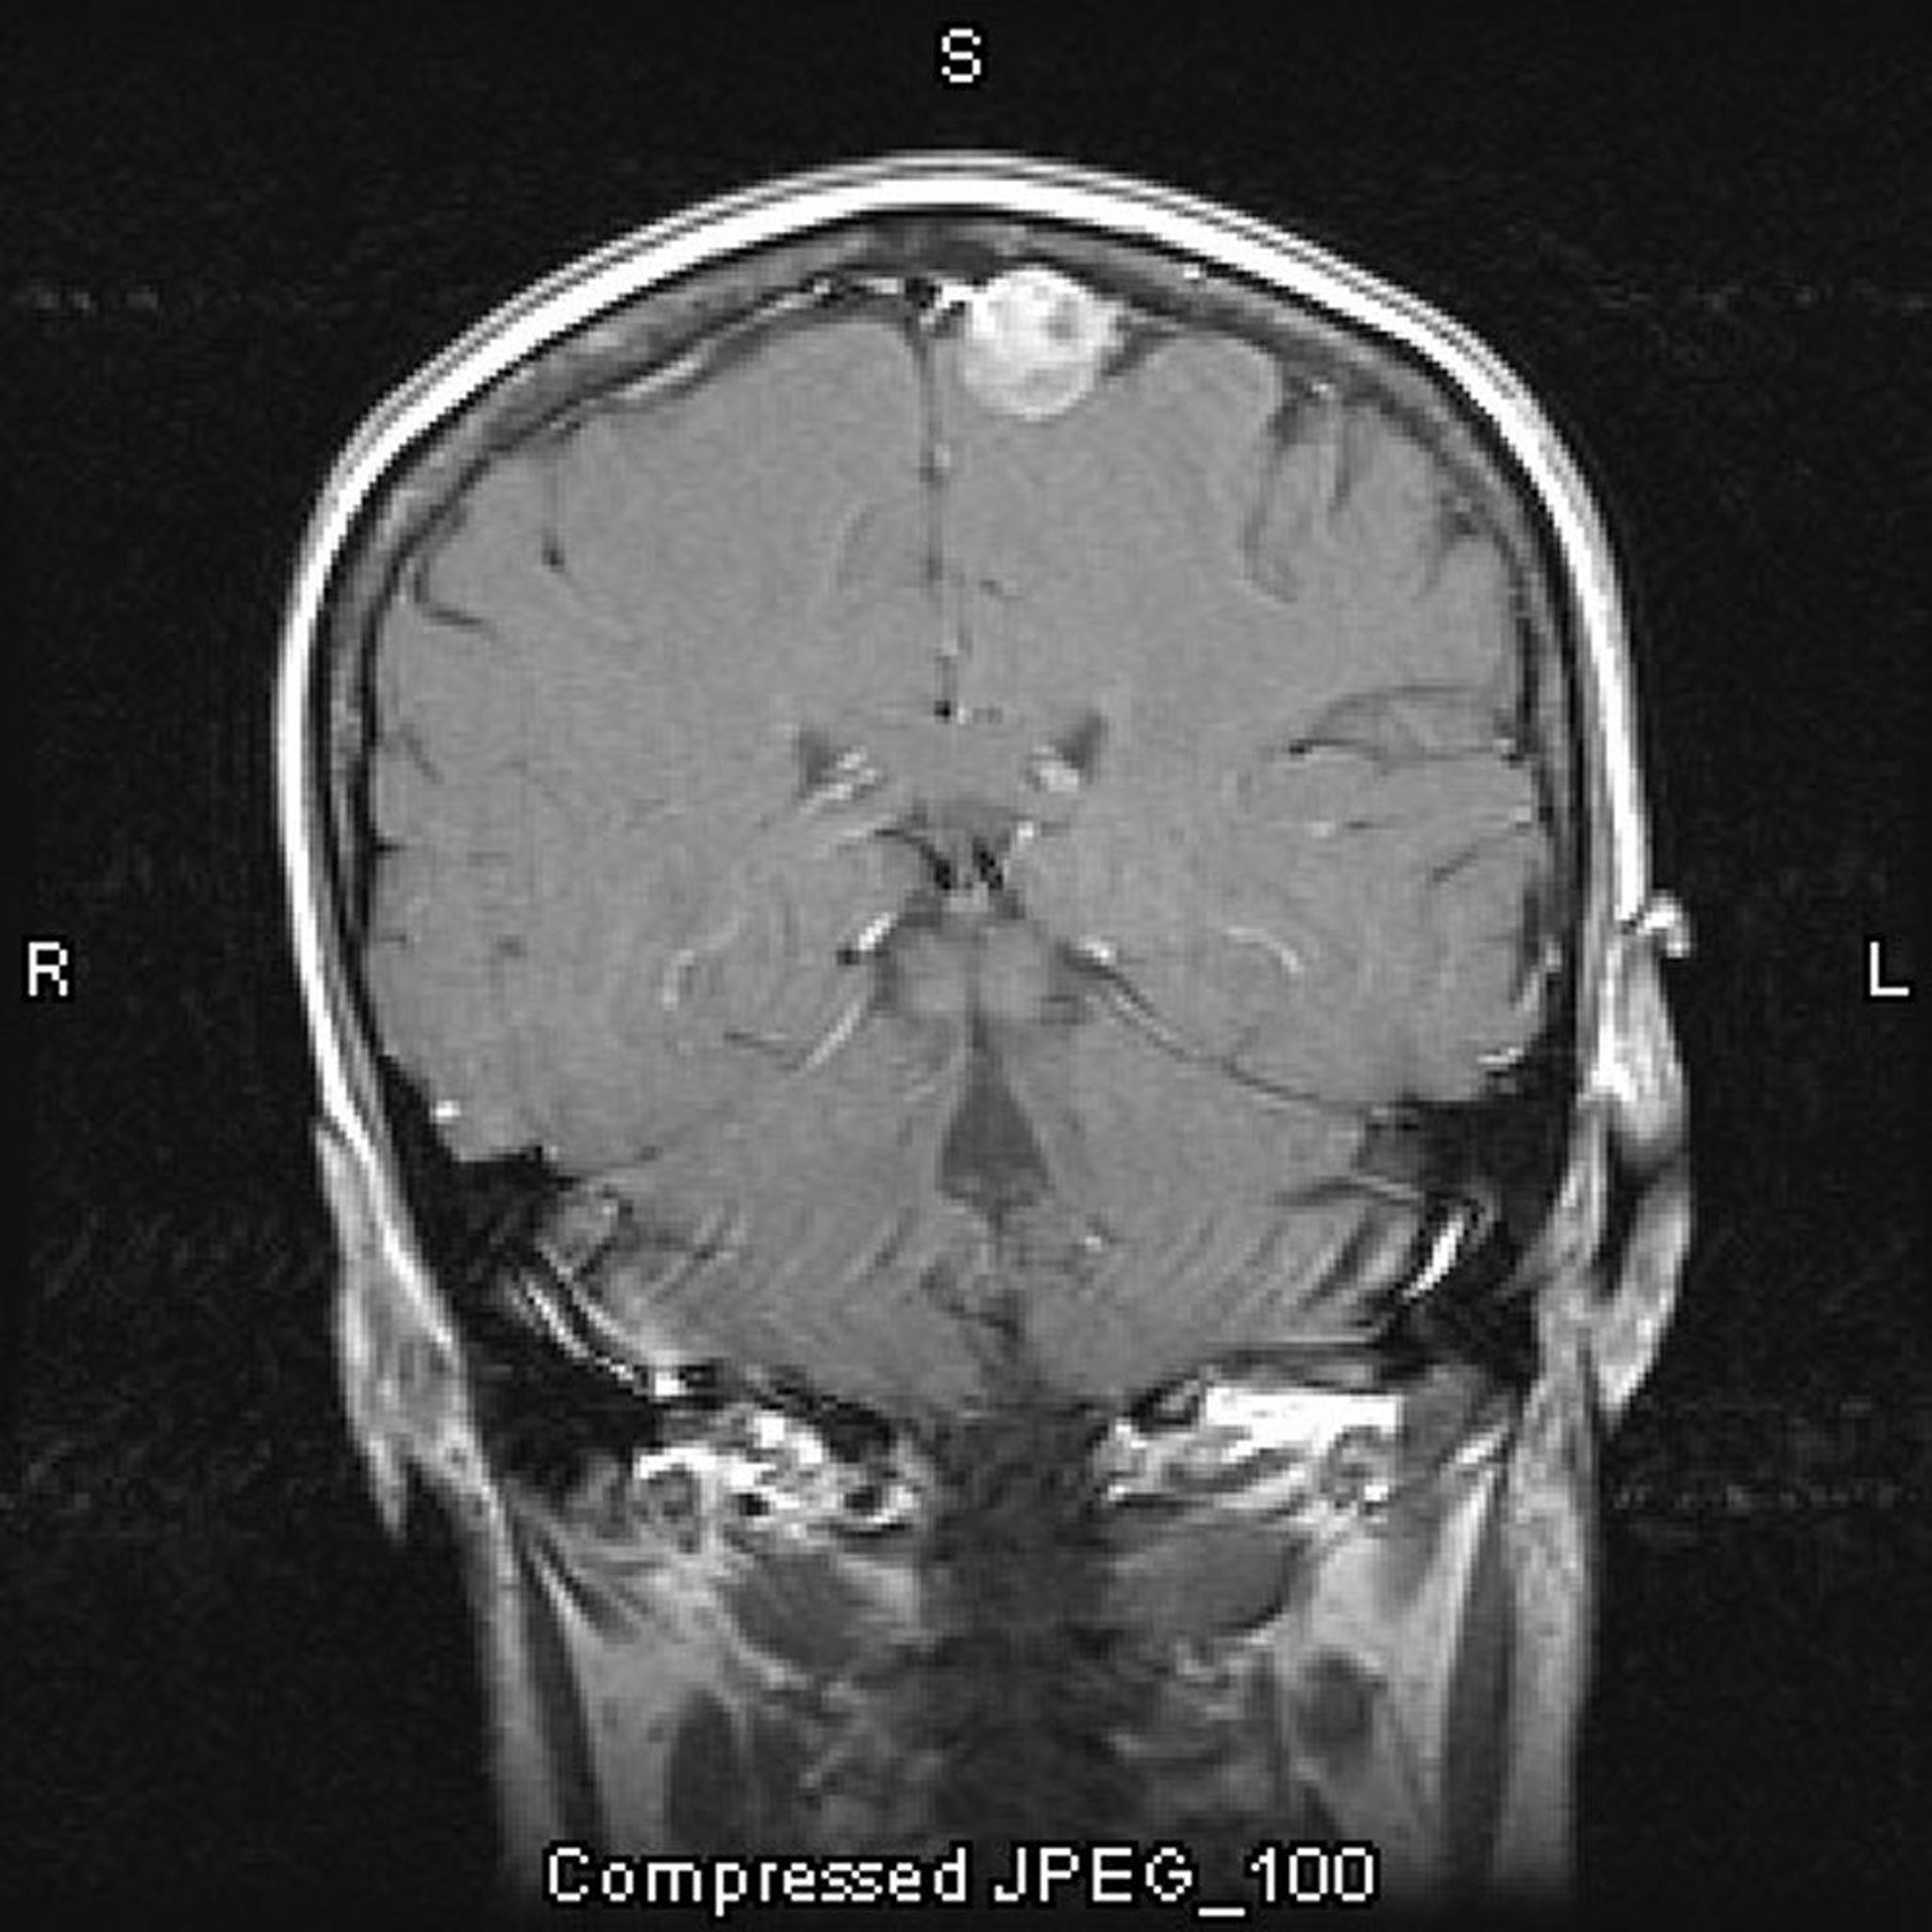

Méningiome parasagittal

Cette IRM avec injection de produit de contraste montre un méningiome. L'emplacement parasagittal est typique des méningiomes.

Image courtoisie de William R. Shapiro, MD.